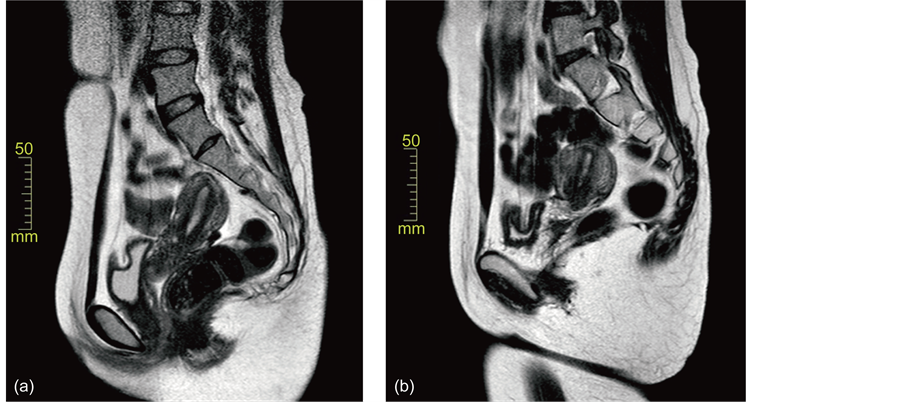

Twenty patients with endometrial cancer received conservative MPA treatment. Patients’ characteristics are summarized in Table 1. The patients’ ages ranged 23 to 37 years old (average, 30.7 ± 3.4). Pathological diagnoses were 18 with endometrioid adenocarcinoma and two with adenosquamous cell carcinoma, their grades being 19 with G1 and one with G2. The patient’s BMI ranged 17.1 to 42.2 (26.5 ± 7.5). Treated period ranged 4 to 11 (6.3 ± 1.5). In Figure 1, changes of the endometrial lesions on MRI (T2-weighted) in Case 19are shown. Pathological changes of the endometrial lesions in Case 1 were also shown in Figure 2.

Figure 1. Changes of the endometrial lesions on the MRI (T2-weighted) in Case 19. (a) Before therapy, a slightly thickened endometrial lesion in seen; (b) the thickened lesion disappeared six months after the therapy.